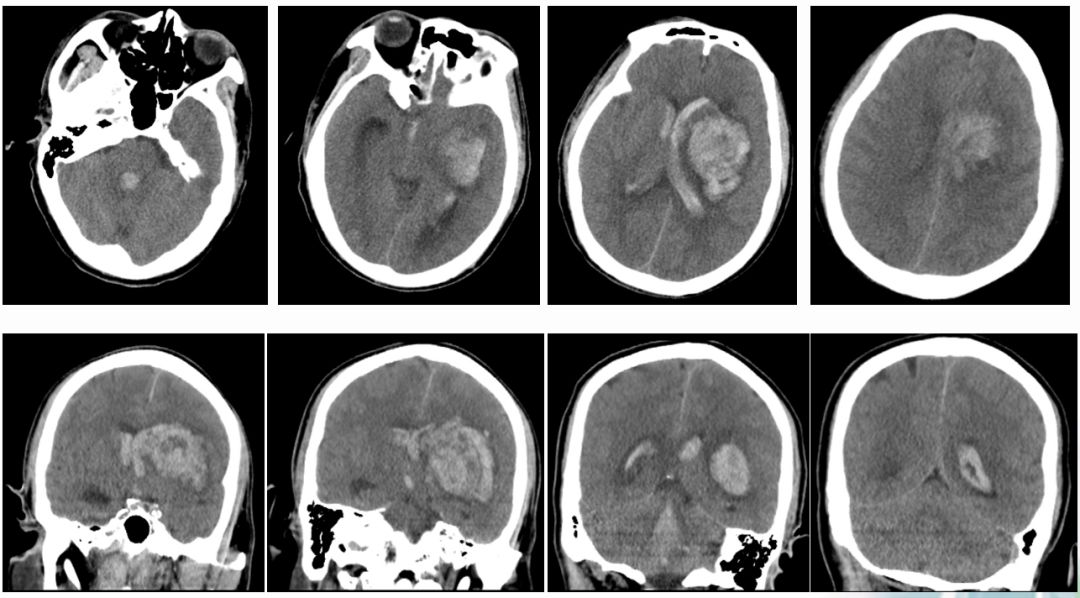

术前CT

术前MR

ASPECTS评分 8分

术前造影:

串联病变

双颈动脉支架

术后CT

24H

36H

45H

术前NIHSS评分 6分

术后24hNIHSS评分 1分

术后36hNIHSS评分 2分

术后45hNIHSS评分 22分